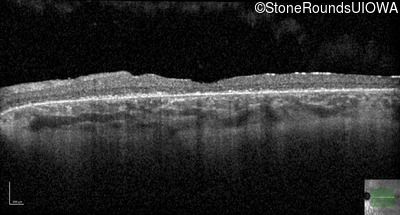

Optical Coherence Tomography - Left - 20/200 +2

Exemplar / OCT Stack

OCT Stack